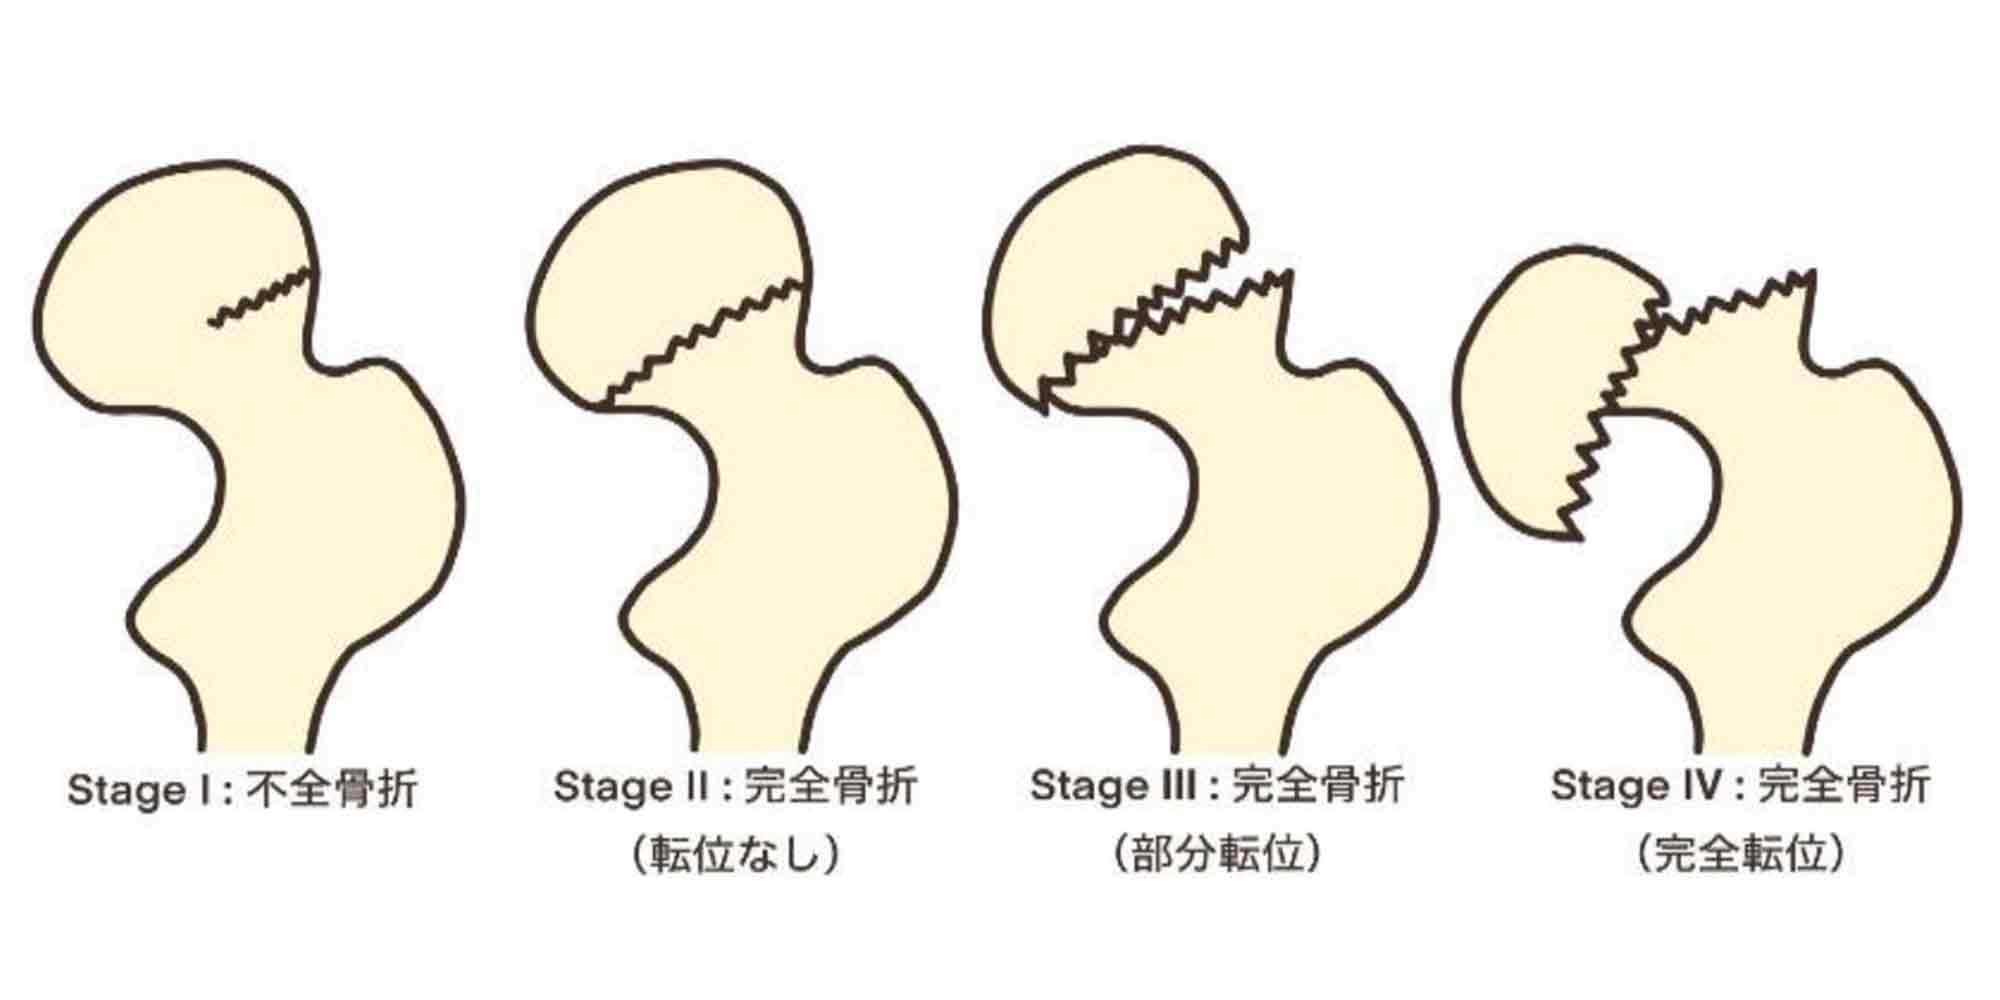

■ 大腿骨頸部骨折

大腿骨頸部骨折は、転倒や転落などによって大腿骨の根もとの部分が折れてしまった 状態です。40歳から年齢とともに増加し、70歳以上になると急激に発症率が高まります。また、約8割が女性です。

高齢の女性よく見られるのは、女性の疾患に多い骨粗鬆症が年齢とともに進行し、骨が少しずつもろくなっていくことが大きな原因です。